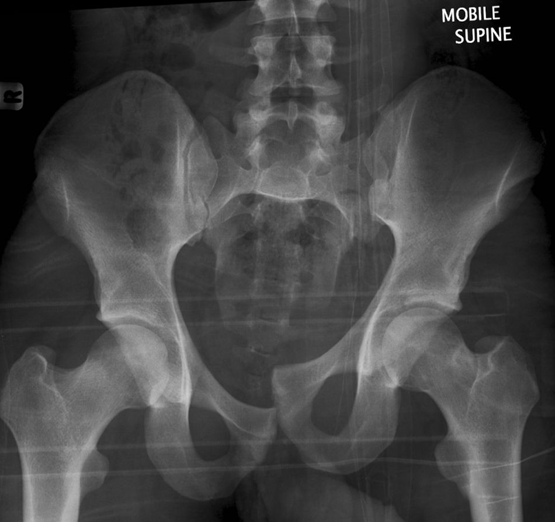

(1)Malgaigne 骨折

指垂直不稳定骨盆骨折,骨折累及双侧耻骨支、骶髂关节或者骶骨。

(6)Straddle 骨折

双侧耻骨上下支骨折。